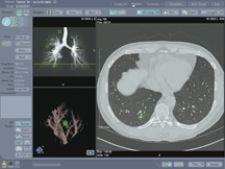

Vitrea solution integrates Vitrea workstation with R2's ImageChecker CT Lung CAD software for multislice CT.

What may give CT a leg up on X-ray is Computer Aided Detection (CAD) for CT lung, software that highlights suspicious nodules in lung morphology and assesses nodule size changes over time to track progression of cancer therapy. CAD has also made its mark by demonstrating its capacity to provide radiologists with enhanced views of ultra-small pulmonary nodules from as little as 6 mm in size.

Solutions available on the market today include Siemens’ syngo LungCare and R2 Technology’s ImageChecker CT Lung Nodule application. As CAD’s performance in detecting lesions and nodules in the lung is not fully known, vendors are careful to point out that the intended use of their CAD solutions is as a second reader only – not a substitute. “CAD will increasingly become the standard of care with CT chest exams to detect and manage actionable lung nodules and pulmonary artery filling defects such as emboli to provide additional decision support,” indicated Terry Chang, director of CT CAD Marketing, R2 Technology Inc.

In recent studies involving a multireader receiver operating characteristic (ROC), potential nodules that were overlooked showed a 26 percent reduction with R2’s ImageChecker, as well as average reader improvement in radiologists to detect nodules between 4 and 30 mm in size. Another retrospective study showed that significant nodules were overlooked in 33 percent of cases, bolstering the need for technology that supports readers. Should CAD prove an effective diagnostic aid for CT lung exams, CT may likely outperform chest X-rays in screening for lung cancer.